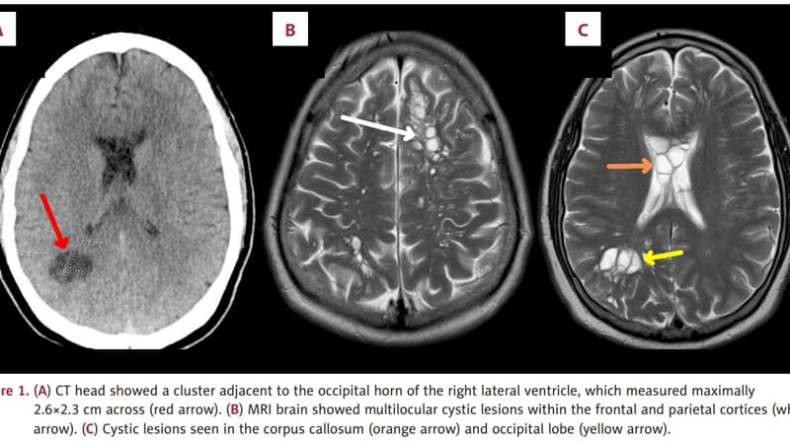

Aux États-Unis, un habitant de Floride a souffert de longues migraines récurrentes. Des imageries médicales de son cerveau ont décelé des parasites.

Le porc ne se mange jamais cru [ne se mange jamais car prohibé par la religion musulmane, ndlr]. Ce jeudi 7 mars, un cas intrigant a été rapporté dans l’American Journal of Case Reports. Les faits remontent au 8 novembre 2023, lorsqu’un homme de 52 ans s’est présenté aux médecins d’Orlando, une ville de l’État de Floride, aux États-Unis, selon BFMTV.

Il a, au départ, simplement déclaré souffrir de migraines chroniques depuis 4 mois. Comme l’expliquent les médecins dans leur compte-rendu, il a été décidé de mener une série de tests pour trouver l’origine de ces maux.

Ces grosses masses étaient en réalité des parasites et plus particulièrement des larves de ténia, un ver pouvant atteindre 4 à 8 mètres de longueur à l’âge adulte.